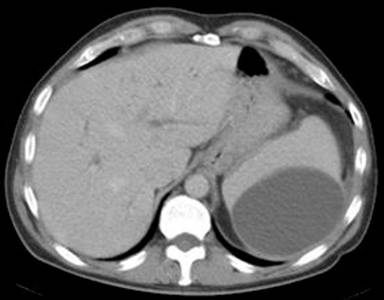

A 47-year-old man with known alcoholic pancreatitis for 10 years was admitted as an emergency with a twenty hour history of left upper quadrant pain radiating to his left shoulder. He was apyrexial and haemodynamically stable. His serum amylase was 245 U/L (reference range: 0-100 U/L) and the white cell count was 17.5 x109/L (reference range: 4-11 x109/L). A CT scan (Figure 1) showed a large sub-capsular fluid collection in his spleen. Twenty four hours later, he suddenly complained of worsening pain and became hypotensive. An urgent CT scan confirmed active bleeding with disruption of the sub-capsular splenic haematoma (Figure 2).

Figure 1. Splenic sub-capsular haematoma (Case #1). |